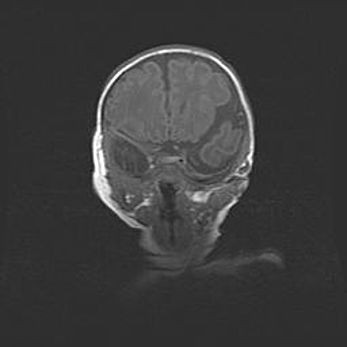

Мальформация Денди-Уокера. Киста задней черепной ямки.

Агенезия мозолистого тела.

Возраст: 2,5 месяца

Вес: 2420 г

Пол: женский

Окружность головы: 37 см

Срок гестации: 32 недели

Мальформация Денди—Уокера — редкий вид патологии ЦНС, представляющий собой врожденный порок развития каудального отдела ствола и червя мозжечка, ведущий к неполному раскрытию срединной (Мажанди) и латеральных (Лушка) апертур IV желудочка мозга. Для этогно синдрома характерна триада симптомов: гипотрофия червя мозжечка и/или полушарий мозжечка, кисты задней черепной ямки, гидроцефалия различной степени. В 70% случаев порок сочетается и с другими аномалиями головного мозга, в частности с агенезией мозолистого тела.